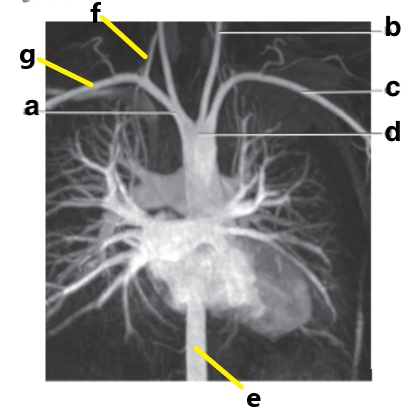

Which letter is the Left common carotid ?

b

Which letter is the left subclavian artery ?

Which letter is the Right common carotid artery ?

d

What is letter a ?

Brachiocephalic trunk

Which letter is the Descending aorta ?

f

Which letter is the ascending aorta ?

Which letter is the Right vertebral artery ?

c

Which letter is the right subclavian artery ?

g

a

Which letter is the brachiocephalic trunk ?